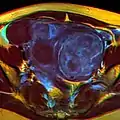

Multiple uterine leiomyoma

Large subserosal fibroid

Multiple uterine leiomyoma with calcification

Fibroids are monoclonal tumors and approximately 40–50% show karyotypically detectable chromosomal abnormalities. When multiple fibroids are present they frequently have unrelated genetic defects. Specific mutations of the MED12 protein have been noted in 70 percent of fibroids.[29]